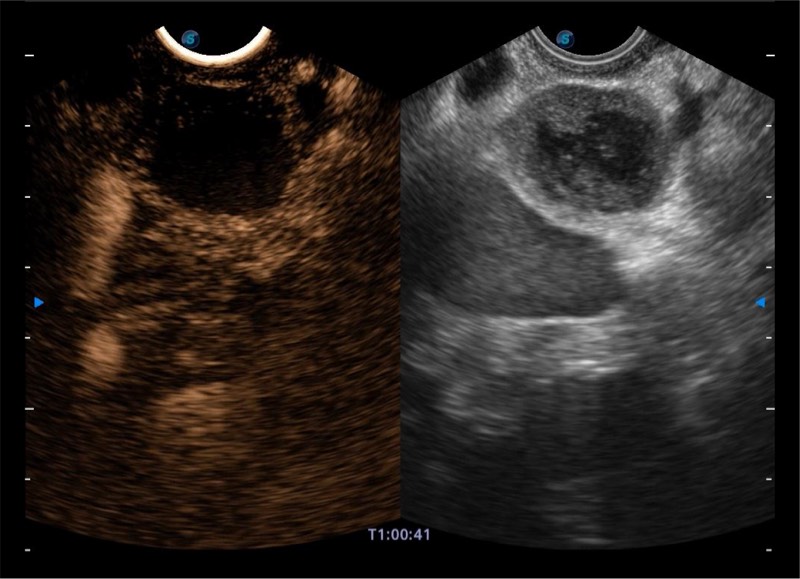

基于二十年的超声技术积累,开立提供了最新一代的独立超声主机,在提供高质量图像的同时满足多学科使用。具备常见多普勒技术并提供弹性成像、声学造影等高端影像技术。新一代传感器具有更强的抗干扰能力并减少图像伪影。

150°超声扫描角度

4-12MHZ宽频输出